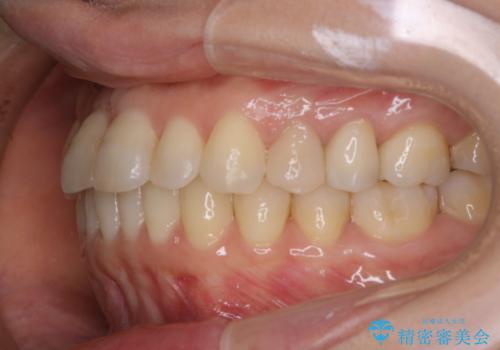

矯正治療とセラミック治療が終了後のPMTC

- 矯正治療とセラミック治療の総合治療が終了したため、クリーニングをしっかりとしてからメンテナンスに入りたいとのことでした。PMTC30分コースを行いました。

矯正治療やセラミックなどによる被せ物の治療終了のタイミングではクリーニングを行い、汚れや着色の除去、歯と歯の間・歯と歯肉との境目などのケアをしっかりすることをおすすめしています。

ご自身での歯ブラシ・セルフケアを行うと同時に、定期的なクリーニング(PMTC)を行うことで、いつまでも健康な歯を保つことができます。